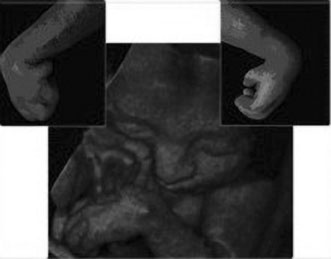

THREE-DIMENSIONAL ULTRASOUND

Three-dimensional ultrasound is currently investigational. It is most commonly used at tertiary care centers and is commercially available for patients to obtain a keepsake image of their unborn child. Potential advantages include the ability to visualize fetal anatomy better and possibly change a patient's diagnosis through improved visibility (Figs. 13 and 14). No confirmed adverse biologic effects on patients or instrument operators caused by exposure have been demonstrated.32

Fig. 13. Three-dimensional ultrasound image showing midline facial cleft. Image courtesy of GE Medical Systems.

Fig. 14. Three-dimensional ultrasound image of twin gestation. Image courtesy of GE Medical Systems.